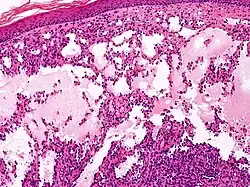

Microscopicamente, as vesículas em um linfangioma circunscrito são canais linfáticos dilatados expandindo a derme papilar. Eles podem ser associados com acantose e hiperqueratose. Há muitos canais na derme superior, muitas vezes se estendendo para o tecido subcutâneo (a camada mais profunda da derme, contendo gordura e tecido conjuntivo). Os vasos mais profundos têm grande calibre com paredes espessas que contêm musculatura lisa. O lúmen é preenchido com fluido linfático, mas muitas vezes contém glóbulos vermelhos, linfócitos, macrófagos, e neutrófilos. Os canais são revestidos com células endoteliais planas. O interstício tem muitas células linfóides e mostra evidência de fibroplasia (a formação de tecido fibroso). Nódulos (uma pequena massa de tecido ou agregação de células) em linfangiomas cavernosos são grandes canais, irregulares, na derme reticular e tecido subcutâneo que são revestidos por uma camada única de células endoteliais e uma camada incompleta de músculo liso. O estroma é constituído por tecido conjuntivo frouxo com uma grande quantidade de células inflamatórias. Estes tumores geralmente penetram a musculatura. O higroma cístico é histologicamente indistinguível de um linfangioma cavernoso. [7]